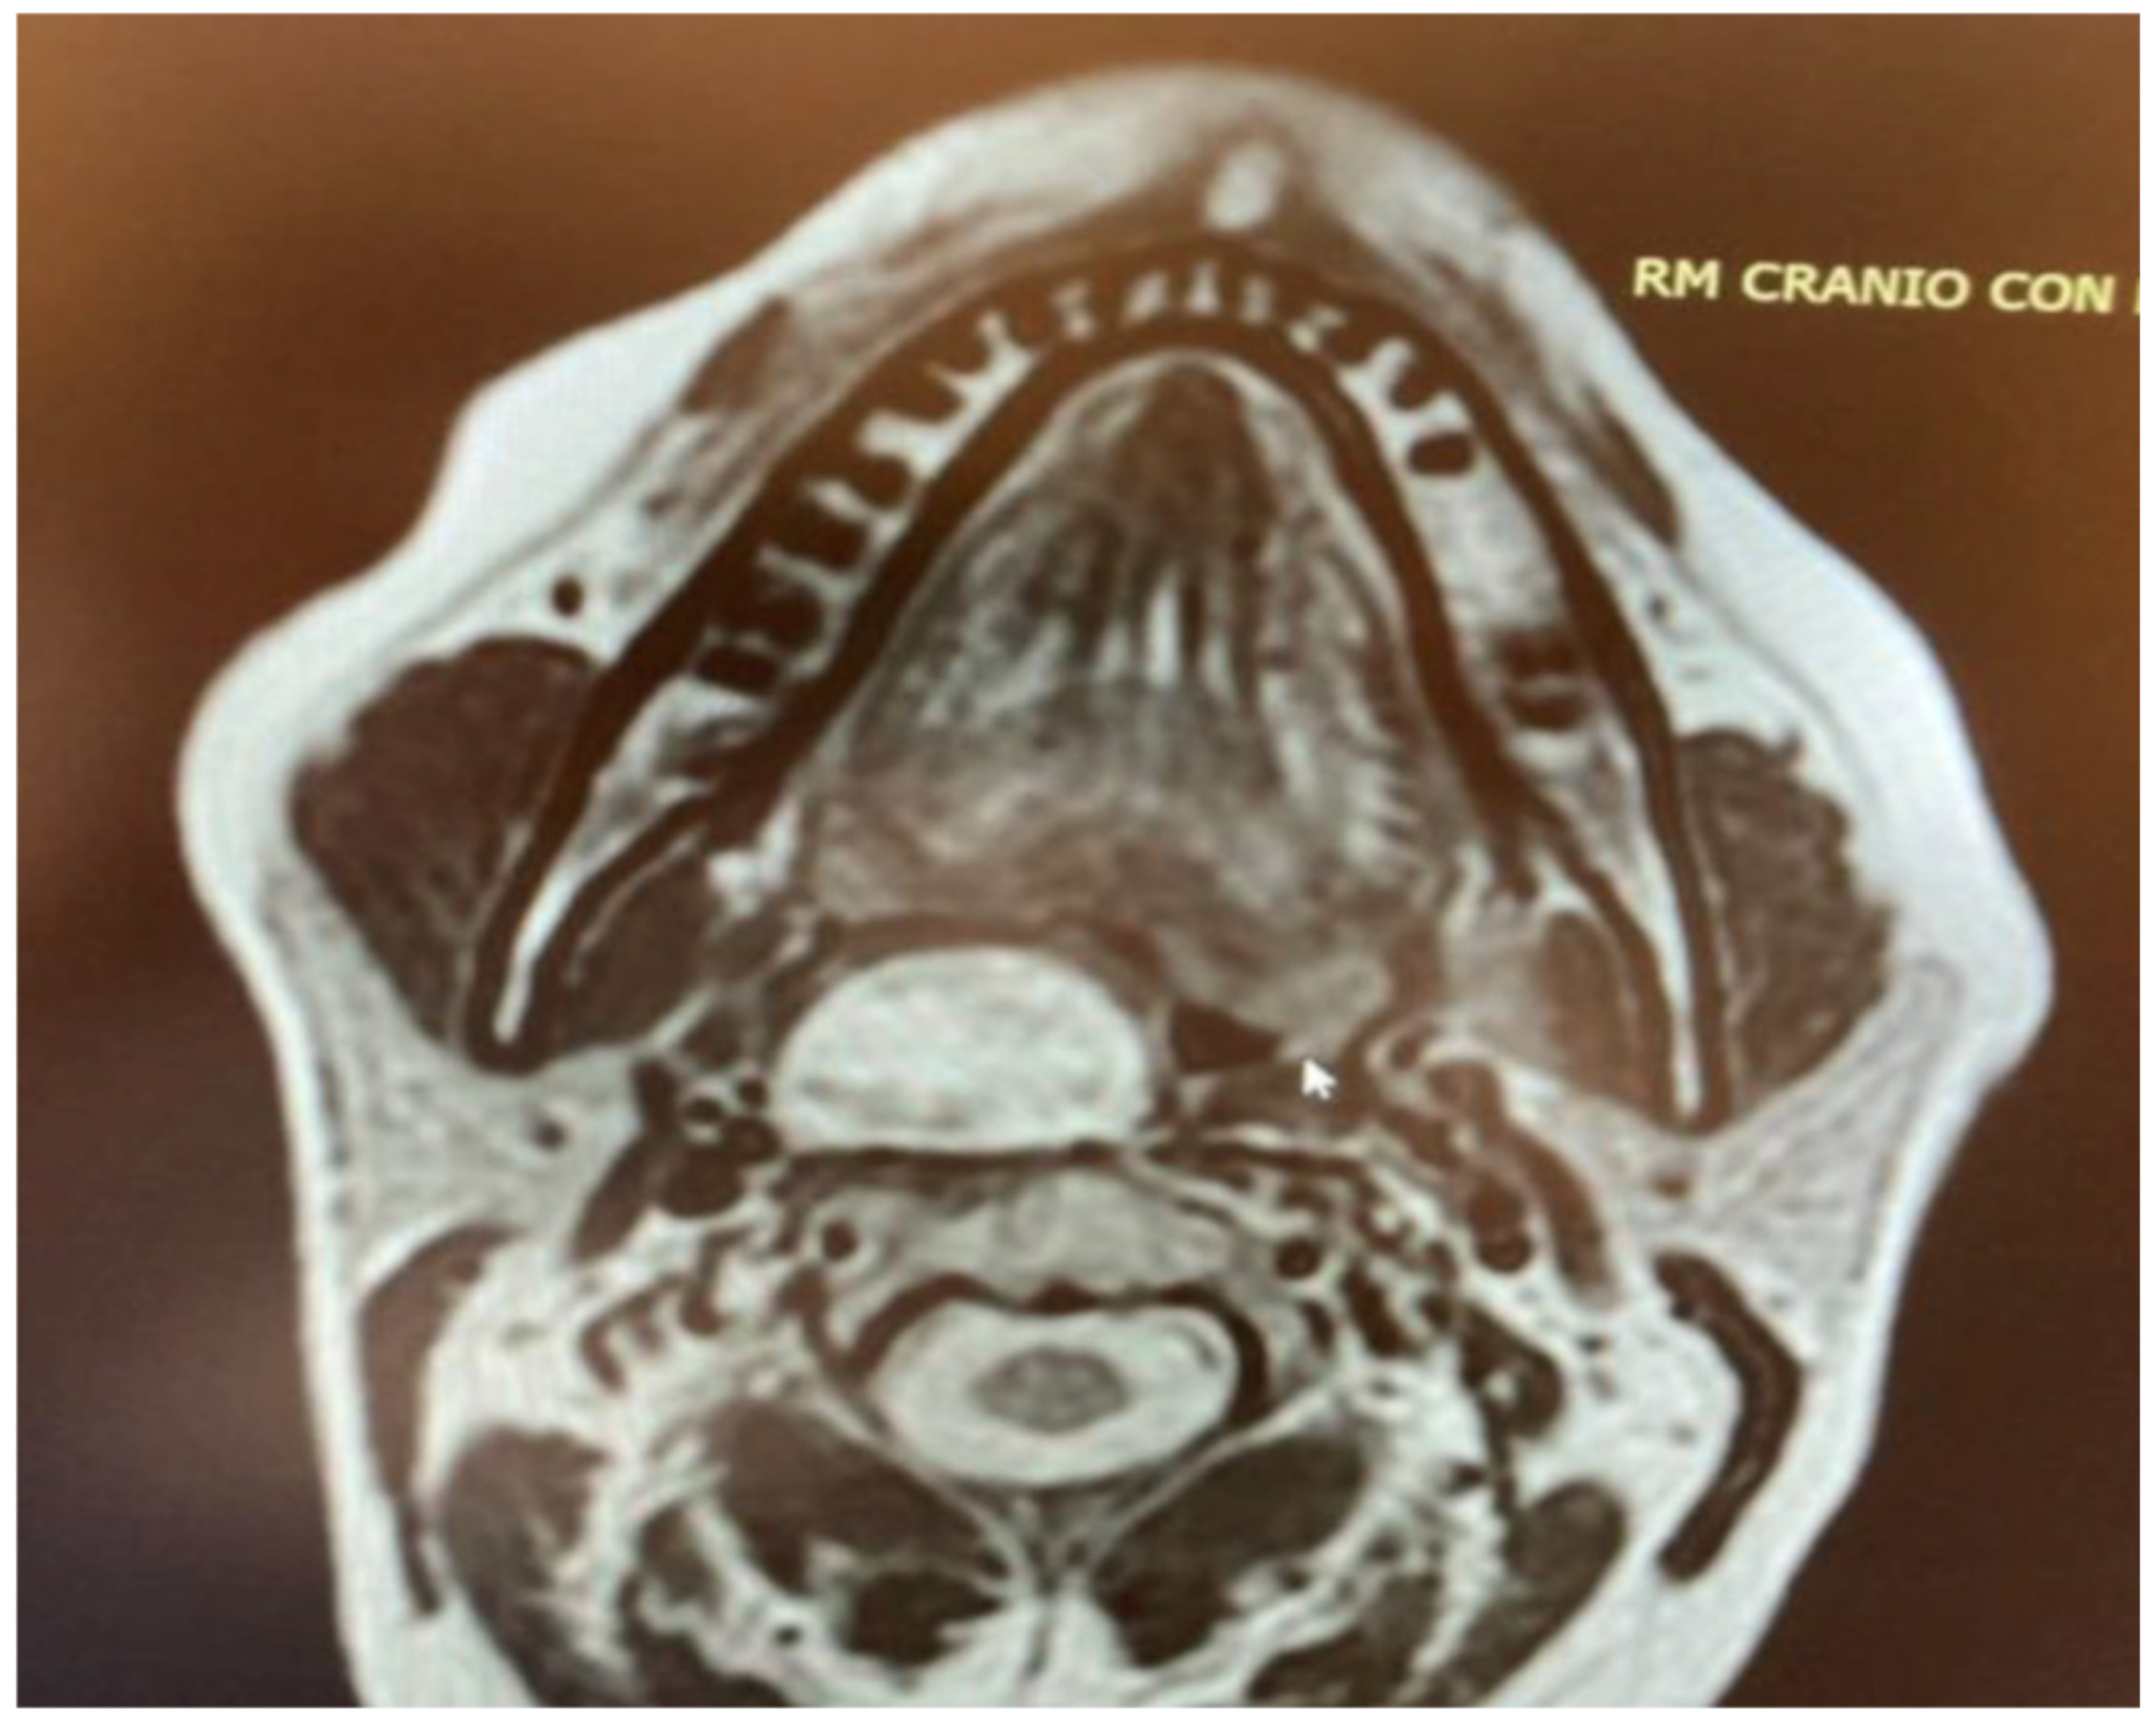

For the final two lesions, which did not arise within the PPS, the issue of favorable major vessel displacement was not a primary concern. Both the schwannoma of the MS (Figure 5) and the NPA (Figure 6) were located outside the immediate vicinity of major vessels posing a positional challenge. Therefore, the transoral approach was feasible due to their favorable location and benign characteristics, both clinically and radiologically confirmed by MRI.

Figure 5. Masticator space schwannoma.